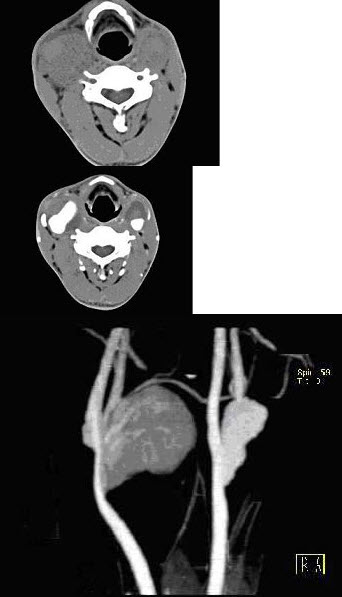

20、单项选择题  术前检查中发现团块性病灶,最可能的诊断是()

D.以上都有可能

E.以上都不是

点击查看答案